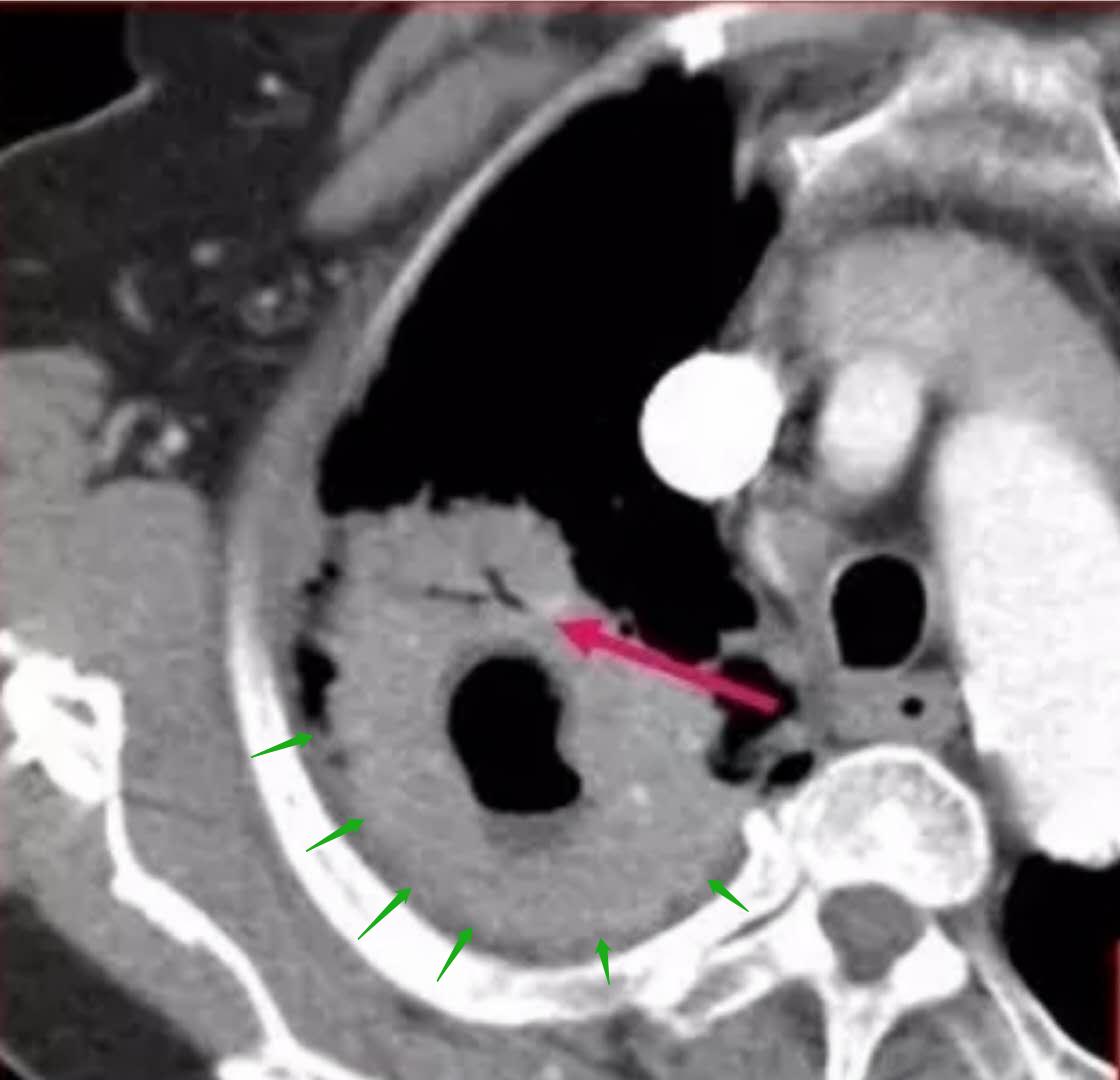

看到这张片子,我们放心多了!

这应该是一个炎症性病灶,不支持肺癌,依据如下:

1.绿色箭头显示,病灶强化很均匀,几乎看不到任何低密度区。

豪大夫前面的文章里提过,肺癌一般是轻度不均匀强化;而结核因为常造成干酪样坏死,血管破坏比较彻底,一般是不强化或者边缘薄环状强化;炎症性病变多为明显均匀强化。所以图中绿色箭头区域支持炎症性病变——肺脓肿。

2.在洞壁上,可以看到一段与洞壁平行的支气管,这个征象强烈支持炎症性病变。

这个支持炎症的征象需要满足两个要素:

(1)病灶为实性肿块,不能伴有磨玻璃,因为伴有磨玻璃的空洞往往是假性空洞;

(2)支气管要与空洞壁平行,不能是垂直的。

这位老太太很幸运,影像都支持炎症性病变(肺脓肿),不符合肺癌,我们建议她先抗炎治疗复查。

后来化验血象,白细胞明显升高,也支持我们的诊断。

经过大约两个多月的抗炎治疗,复查基本吸收了。